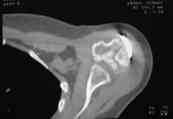

В момент осмотра: нормостеническая конституция, по передней поверхности плечевого сустава – рубец. Рука в положении приведения. Отведение не более 10 град, дальнейшие движения с лопаткой до 20-25 град. Амплитуда сгибания-разгибания 10-15 град. Ротация отсутствует. Пальпаторно - выраженная болезненность над суставом, особенно в проекции клювовидного отростка. При попытках пассивных движений – боль. Рентгенограммы и результаты КТ приложены(b2(3)_xr.jpg, b1(6)_ct.jpg).

Диагноз: неправильно сросшийся в условиях накостного остеосинтеза оскольчатый перелом головки левой плечевой кости (11-С3.2), асептический некроз головки плечевой кости, смешанная артро-миогенная контрактура левого плечевого сустава; демиелинизирующая нейропатия левого локтевого нерва.

Анализ ситуации позволяет считать, что основными причинами контрактуры являются неправильная репозиция фрагментов головки (разворот кверху и кзади), асептический некроз головки плечевой кости (отчетливое склерозирование на СТ).